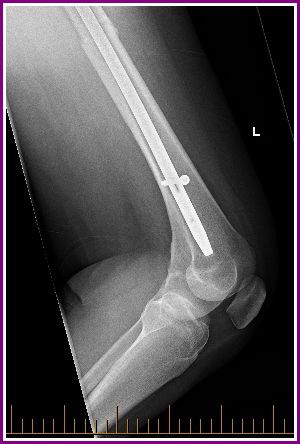

Today was my much anticipated appointment with my Orthopaedic Surgeon and it went pretty much as I expected really. My leg is still broken and it is showing minimal signs of healing but all to be expected due to the nature of the break.

He wants to see me again in 3 months, with further x rays, (not 6 months as expected) as he is a little concerned that the screw above the knee ( called the dynamic screw) may have to be removed. I literally dodged a bullet today in regards to having that kind of surgery as he could see that the screw still has some capability to move…a good thing apparently.